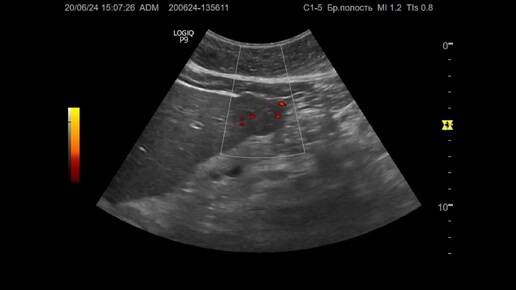

Ультразвуковая диагностика (УЗИ). Доктор Иогансен. Видеопримеры. Выпуск 86. Опухоль печени (4).